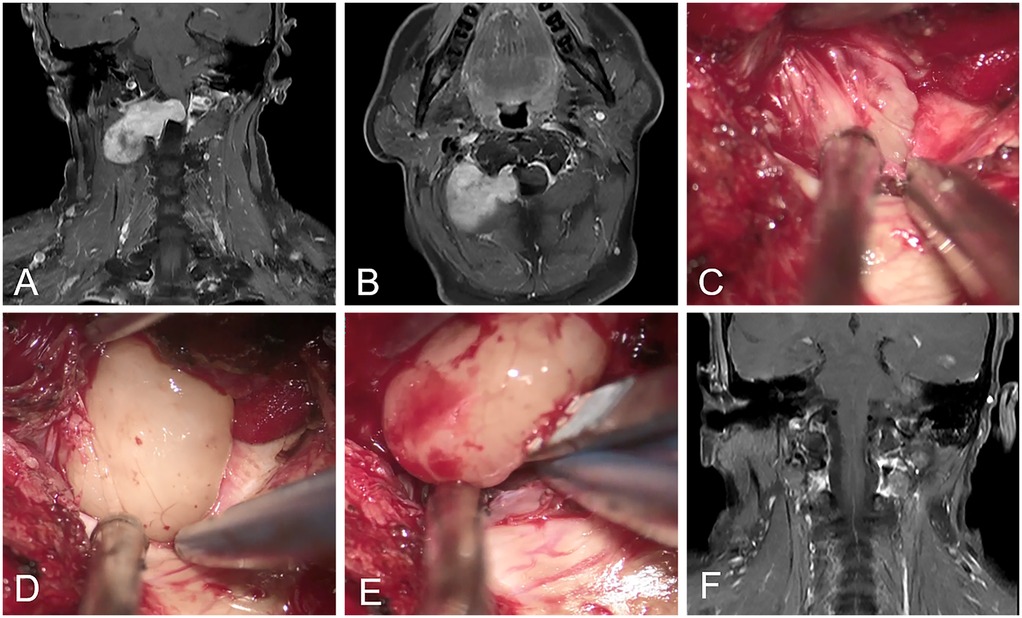

Tailored resection of spinal dumbbell schwannomas using transforaminal and modified epidural trans dural sleeve approaches with hemilaminectomy

Background and purpose: Surgical resection of dumbbell-shaped spinal schwannomas, which involve both intra-extradural and intra-extraspinal components, presents significant technical challenges. This study aimed to evaluate the safety and efficacy of the transforaminal and modified epidural trans dural sleeve approaches with hemilaminectomy without dural incision for the tailored resection of spinal dumbbell-shaped tumors in comparison with conventional laminectomy. Methods: This was a retrospective, observational cohort study. Between May 2017 and November 2024. A total of 44 patients with extra-intraspinal dumbbell-shaped tumors who underwent tumor resection were included in the analysis. Procedure-related data, postprocedural serious adverse events (SAEs), clinical and imaging outcomes were evaluated. Results: All patients (44 tumors) were successfully treated, of which 20 patients were treated through the epidural trans-dural sleeve approach (epidural approach group) and 24 patients were treated through the conventional laminectomy and dural incision (conventional approach group). Gross total resection was performed in 95.5% (42/44) patients, with 2 cases of residual tumor in the conventional approach group. A total of 12 (27.3%) patients experienced at least one SAE before discharge, including 3 (15.0%) in the epidural approach group and 9 (37.5%) in the conventional approach group (P=0.095). Blood transfusions were performed in 10 (41.7%) patients in the conventional approach group, and no patients were required in the epidural approach group (P=0.003). Multivariate analysis revealed that intraprocedural estimated blood loss ≥ 350 ml was significantly associated with SAEs during hospitalization (OR: 6.6; 95%CI: 1.5-29.7; P=0.014). During the follow-up duration of 28.0 (9.5, 51.0) months, 42 patients were classified as ASIA grade E, and 2 as grade D. No tumor recurrence was detected during the imaging follow-up. Conclusion: Epidural trans-dural sleeve approach can be a safe and effective method for treating spinal dumbbell-shaped tumors, with relatively lower intraprocedural blood loss and transfusion rates compared to conventional techniques. Intraprocedural estimated blood loss ≥ 350 ml was significantly associated with SAEs during hospitalization.